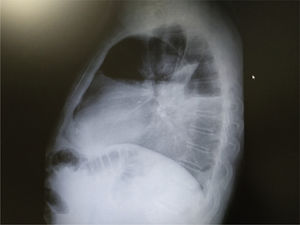

Presentamos el caso de un paciente de 63 años que consulta por disnea desde hace 15 días que se ha convertido a medianos esfuerzos desde hace unos meses. Exfumador de 10-15 cigarros al día hasta hace 20 años. Exposición laboral al amianto. Se efectúa radiografía de tórax urgente desde atención primaria con el siguiente resultado:

- •Radiografía de tórax de perfil (fig. 2): ángulo costofrénico borrado.